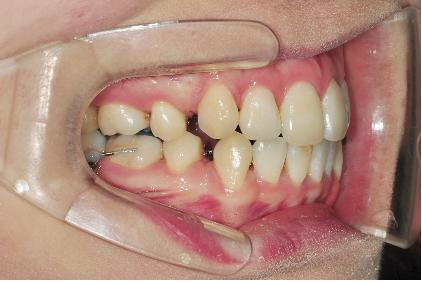

이번 월치료에는 와이어교체와 훅부착하였습니다.

와이어를 약간 더 굵은 걸로 교체하였는데요 ,

와이어를 연결하면서 하나 더 새로운 장치를 부착했어요~

바로 ‘훅’이라는 장치인데요, 이 장치의 역할은 저의 치아치료에서는

앞니쪽부분을 들어올리는 역할을 하게 될 거라구 하셨어요~